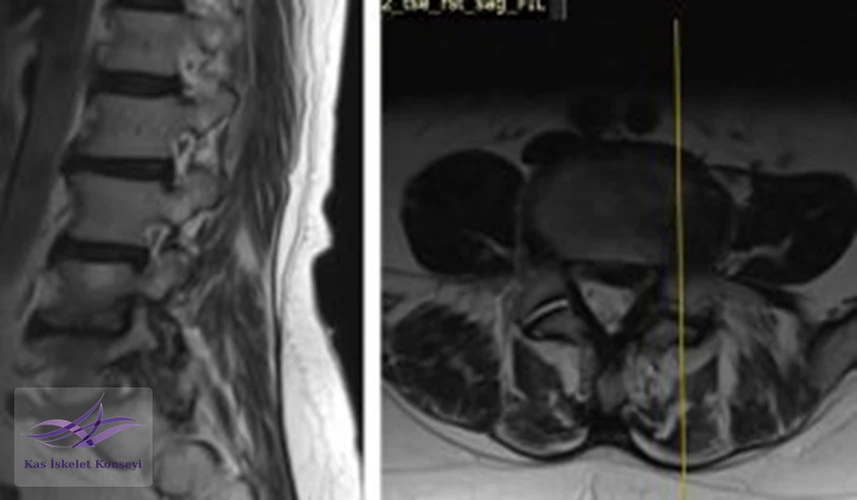

İncelemeler: Lomber MRG: L4-5 diskal bulging ve sol foraminal stenoz var. Kalça MRG istendi, iki yanlı trokanterik bursit rapor edildi.

Resim 1. Lomber MRG, L4-5 seviyesi median kesit.

Resim 2. Lomber MRG, L4-5 seviyesi sağ paramedian kesit.

Resim 3. Lomber MRG, L4-5 seviyesi sol paramedian kesit foramen stenozunu göstermekte.